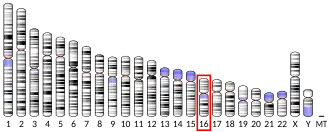

The norepinephrine transporter gene, SLC6A2 is located on human chromosome 16 locus 16q12.2. This gene is encoded by 14 exons.[7] Based on the nucleotide and amino acid sequence, the NET transporter consists of 617 amino acids with 12 membrane-spanning domains. The structural organization of NET is highly homologous to other members of a sodium/chloride-dependent family of neurotransmitter transporters, including dopamine, epinephrine, serotonin and GABA transporters.[7]